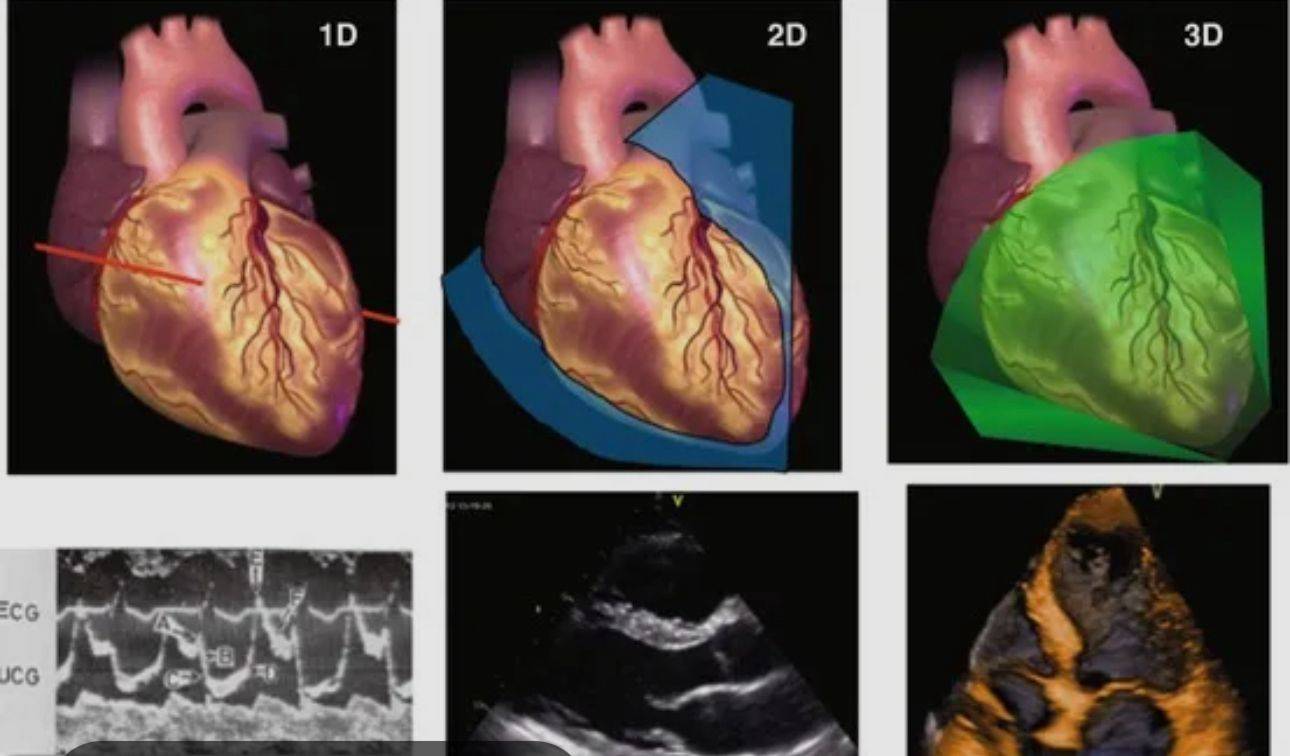

وأشارت إلى أن «التطورات في تكنولوجيا تصوير القلب تضمنت إدخال تخطيط صدى القلب ثلاثي الأبعاد، موضحة أن هذه التقنية تُعد من أهم الإنجازات الحديثة، إذ تمنح الأطباء صورة ثلاثية الأبعاد أكثر وضوحاً ودقة للقلب، مما يساعدهم على تقييم الصمامات والحجرات وتدفق الدم بشكل أدق». واختتمت د. شيماء عبدالمعبود مؤكدة أن «هذه التقنية تتيح للأطباء التخطيط بشكل أكثر فاعلية للتدخلات الجراحية، مثل إصلاح صمامات القلب، وهو ما يمثل نقلة نوعية في تحسين نتائج المرضى وجودة الرعاية القلبية».